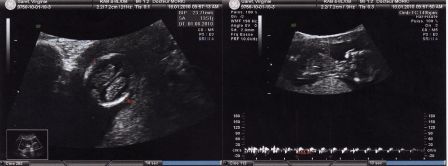

Bébé à 3 mois de grossesse

Par Virginie et Julien Garet le samedi, mai 15 2010, 20:59 - Avant la naissance - Lien permanent